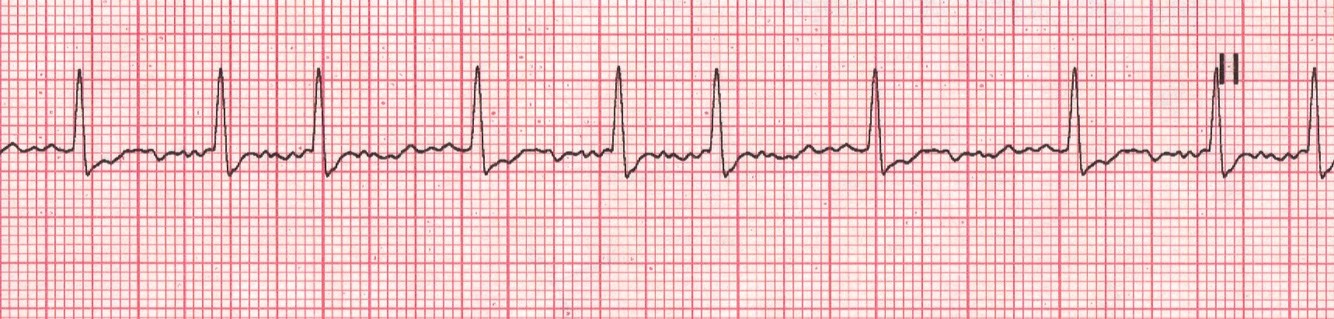

Name that rhythm

Pacemaker spike